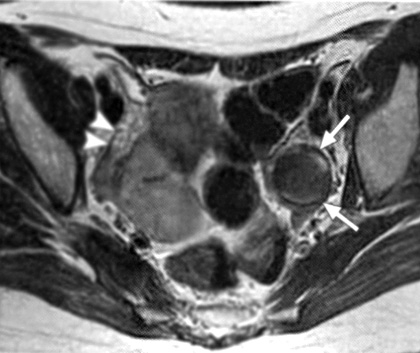

Εικόνα 4. Ωοθηκικά ενδομητριώματα πριν και μετά τη θεραπεία με GnRH-a. Κεφαλή βέλους= δεξιά ωοθήκη (Α,Β). Εγκάρσιες Τ1 (Α) και T2(Β) τομές πριν την έναρξη της θεραπείας, όπου απεικονίζεται μια κύστη υψηλής έντασης (βέλη) που αντιπροσωπεύει ένα ενδομητρίωμα αριστερής ωοθήκης (Γ,Δ). Εγκάρσιες Τ1 και Τ2 τομές μετά τη θεραπεία με GnRH-a. Η κύστη είναι μικρότερη σε μέγεθος, αλλά έχει χαμηλής έντασης σήμα στις Τ2 τομές. Συνεπώς η ορμονική θεραπεία πρέπει να διακοπεί, καθώς η σκιά στο εσωτερικό της κύστης αποτελεί αρνητικό προγνωστικό δείκτη.

Επιπλέον, η μαγνητική τομογραφία κάποιες φορές συμπληρώνει τη διαγνωστική λαπαροσκόπηση, γιατί μπορεί να εντοπίσει εξωπεριτοναϊκές ενδομητριωσικές βλάβες ή εστίες κρυμμένες πίσω από στερρές και εκτεταμένες συμφύσεις, οι οποίες αποφράσσουν μερικώς ή πλήρως τον οπίσθιο δουγλάσειο. Τέλος, αποτελεί μια χρήσιμη μη επεμβατική μέθοδο παρακολούθησης των αποτελεσμάτων της φαρμακευτικής θεραπείας. Βρέθηκε πως η ύπαρξη σκιάς χαμηλής έντασης στις Τ2 ακολουθίες, πριν την έναρξη ή κατά τη διάρκεια της φαρμακευτικής θεραπείας των ενδομητριωμάτων, αποτελεί αρνητικό προγνωστικό παράγοντα. Αυτό οφείλεται στο γεγονός ότι το επιθήλιο της ενδομητριωσικής κύστης λεπτύνεται από την πίεση των προϊόντων του αίματος που συλλέγεται στο εσωτερικό της και το πυκνό αυτό υλικό δεν μπορεί να απορροφηθεί (εικόνα 4).(15)

Η μαγνητική τομογραφία έχει αποδειχθεί χρήσιμη στη διάγνωση των ενδομητριωμάτων, με ευαισθησία και ειδικότητα συγκρίσιμη, και σύμφωνα με κάποιους ερευνητές, μεγαλύτερη της διακολπικής υπερηχογραφίας, αλλά σαφώς και με μεγαλύτερο κόστος ως εξέταση. Συγκεκριμένα ο Takahashi διαπίστωσε πως τόσο η κλασική, όσο και η μαγνητική τομογραφία με καταστολή του λίπους ανιχνεύει όλα σχεδόν τα ενδομητριώματα με διάμετρο μεγαλύτερη των 10 χιλιοστών.(17) Ακόμη η νόσος μπορεί να βρίσκεται σε αρχικό στάδιο, όταν η μαγνητική τομογραφία ανιχνεύει βλάβες μικρότερες των 6 χιλιοστών, ενώ βλάβες μεγαλύτερες των 15 χιλιοστών συσχετίζονται με προχωρημένο στάδιο.(18) Στην κλασική μαγνητική τομογραφία τα ενδομητριώματα εμφανίζονται ως πολλαπλές, ομοιογενείς, υψηλού σήματος μάζες στις Τ1 ακολουθίες και με χαμηλής έντασης σήμα στις Τ2 ακολουθίες ως «σκιά» λόγω της αποδόμησης των προϊόντων του αίματος και της δημιουργίας αιμοσιδηρίνης. Όμως σε περίπτωση πρόσφατου ενεργού ενδομητριώματος η παρουσία αίματος και στις δύο, Τ1 και Τ2, ακολουθίες θα εκδηλώνεται ως υψηλής έντασης σήμα, γεγονός που καθιστά δύσκολη τη διαφοροδιάγνωση από τις αιμορραγικές κύστεις των ωοθηκών. Επίσης, το παχύ ινώδες τοίχωμα της ενδομητριωσικής κύστης εμφανίζεται ως χαμηλής έντασης σήμα στις Τ2 ακολουθίες, με πρώιμη πρόσληψη του σκιαστικού εξαιτίας της ύπαρξης αγγείωσης και μακροφάγων με αιμοσιδηρίνη.